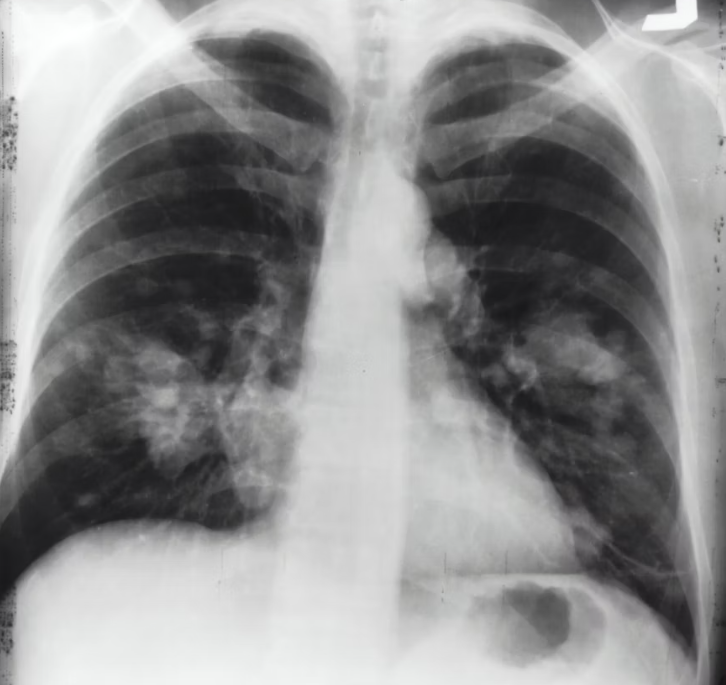

- 이차성 기흉

- 폐기종, 만성폐쇄성폐질환(COPD), 폐결핵 등 기존 질환이 있는 경우

- 중장년층에서 특히 위험

✅ 정기 검진 : 특히 40대 이후에는 흉부 X-ray, CT 검사로 폐 질환 조기 발견